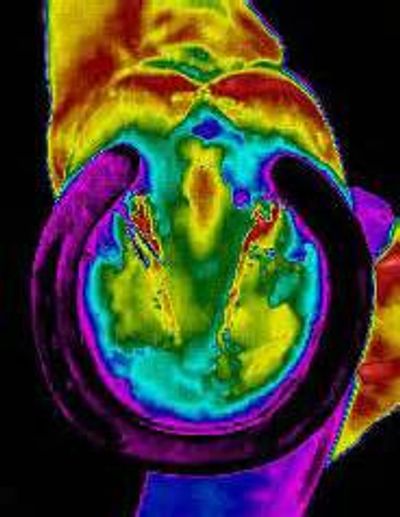

Thermal imaging can accurately locate an Abscess. Notice the heat in these thermal images below . Our thermal imaging cameras are very sensitive and can accurately map the temperature patterns on your horse's hoof allowing the detection of infected areas.

Middle Image: You can see on the right side of the hoof just below the hairline a hot spot. Also if you look at the coronary band is jammed up, showing a hoof imbalance